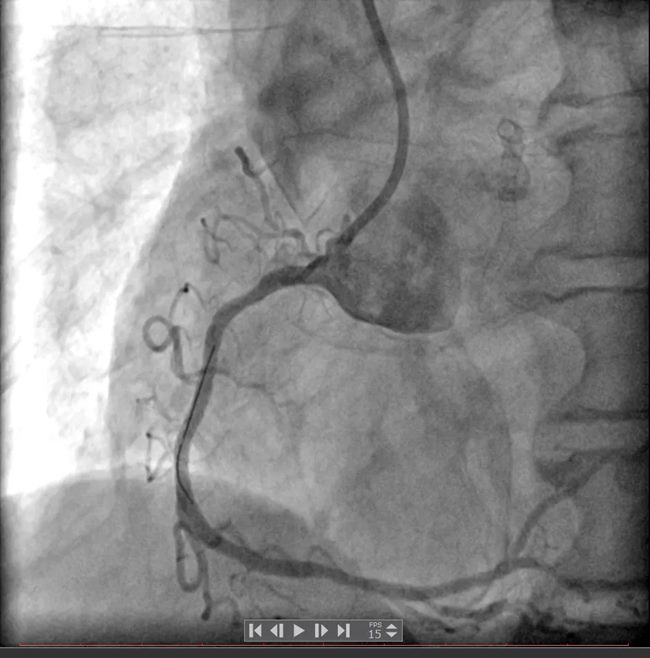

冠脉造影结果显示:左主干未见明显异常,前降支近中段可见支架影,近段支架内狭窄50%,前向血流TIMI3级;回旋支近段次全闭塞,前向血流TIMI2-3级;右冠中段弥漫性狭窄,最重处狭窄95%,前向血流TIMI3级。

最终由手术医师为买买提做了介入治疗:右冠置入支架1枚,回旋支置入药物球囊1枚。